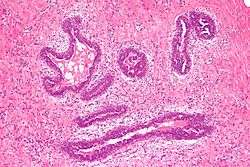

Histology

Early histological features expected to be seen on examination of gynecomastic tissue attained by fine-needle aspiration biopsy include the following: proliferation and lengthening of the ducts, an increase in connective tissue, an increase in inflammation and swelling surrounding the ducts, and an increase in fibroblasts in the connective tissue.[12] Chronic gynecomastia may show different histological features such as increased connective tissue fibrosis, an increase in the number of ducts, less inflammation than in the acute stage of gynecomastia, increased subareolar fat, and hyalinization of the stroma.[12][14] When surgery is performed, the gland is routinely sent to the lab to confirm the presence of gynecomastia and to check for tumors under a microscope. The utility of pathologic examination of breast tissue removed from male adolescent gynecomastia patients has recently been questioned due to the rarity of breast cancer in this population.[35]